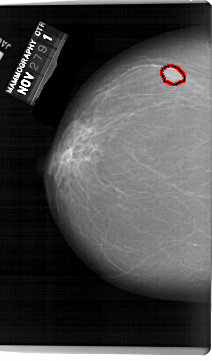

A_1519_1.LEFT_CC

LEFT_CC LINES 6871 PIXELS_PER_LINE 4021 BITS_PER_PIXEL 12 RESOLUTION 43.5 OVERLAY

FILE: A_1519_1.LEFT_CC.OVERLAY

TOTAL_ABNORMALITIES 1

ABNORMALITY 1

LESION_TYPE MASS SHAPE OVAL MARGINS OBSCURED

ASSESSMENT 4

SUBTLETY 5

PATHOLOGY BENIGN

TOTAL_OUTLINES 1

BOUNDARY